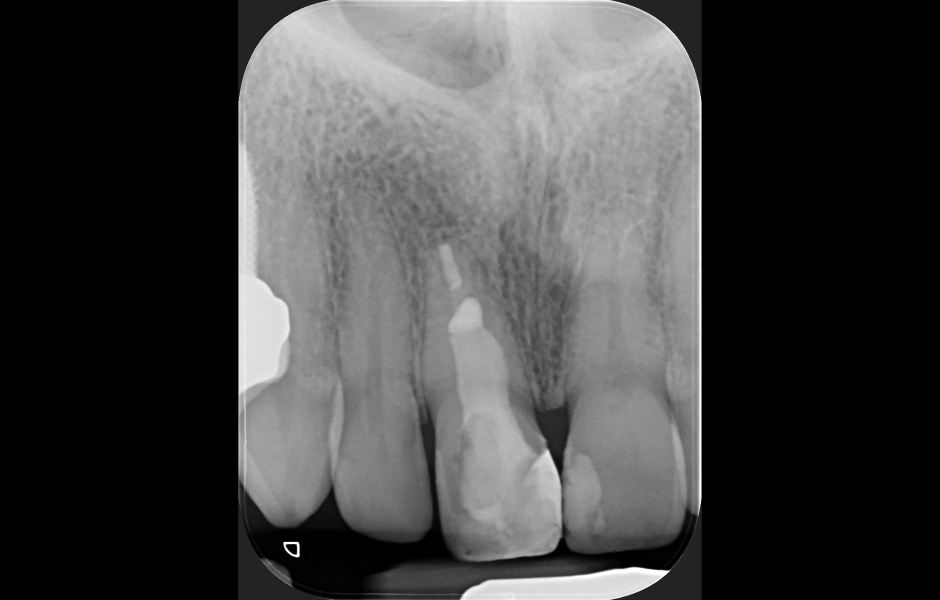

Obr. 1.3: Retrográdní výplň bílým MTA.

Obr. 4.3: Retrográdní výplň MB1, MB2 a isthmu.

Obr. 4.4: Pooperační rentgenový snímek zobrazující retrográdní výplň z bílého MTA.

Kostní okénko a seříznutí apexu kořene se provádí vysokorychlostním násadcem a speciálními vrtáčky či piezokoncovkami, aby bylo možné následně provést ultrazvukovou preparaci apikálních 3 mm kořenového kanálku, které jsou poté zaplněny biokompatibilním materiálem – MTA.